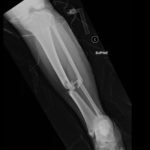

Plain film shows severely comminuted and displaced mid tibia/fibula fractures of bilateral lower extremities (red arrows) and comminuted right fibular head (blue arrow) and proximal shaft fracture (yellow arrow).

The patient in this case was given intravenous cefazolin and was taken to the operating room the same day by orthopedic surgery for bilateral lower extremity tibia and fibula open reduction and internal fixation.